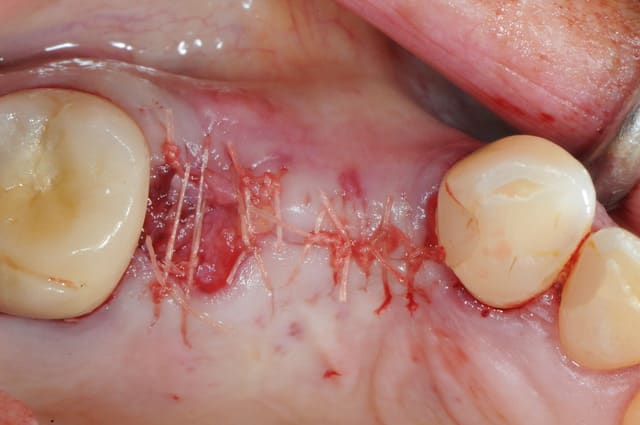

pour débuter ce post je propose un petit cas avec une ROG un comblement alvéolaire et un lambeau pédiculé pour fermer le site d'extraction.

au début incision supra crestal puis lambeau muco-périosté.

avec une simple lame 11 qui tranche le long de gencive palatine. évidemment c'est le plus dure à faire pour éviter de transpercer ou d'avoir d'un coté ou de l'autre une épaisseur trop faible.

résultat à j+5

c'est pas si mal, le "greffon" est rose et ne semble pas s'être nécrosé.

attendons encore 3 mois..

Au maxillaire je procède de la même manière: extraction, curetage, comblement et greffon conjonctif pédiculé. Le punch épithélio-conjonctif ne m'a pas vraiment donné jusqu'à présent de meilleurs résultats que le conjonctif pédiculé et en post-op je trouve que c'est plus douloureux pour le patient.

Avec des instruments adaptés (micro-lames de bistouri N°69 par exemple) et un bon protocole, cela donne de très bons résultats comme le montre la photo de D57